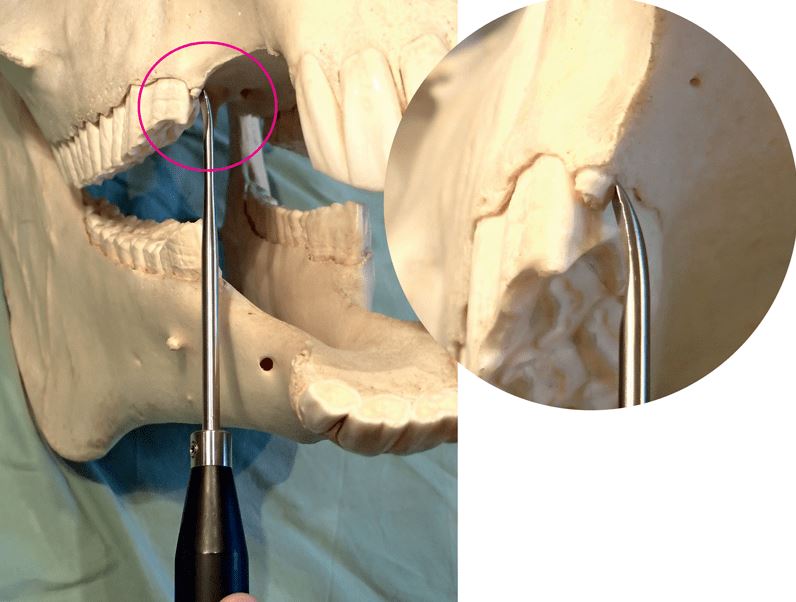

Pegasos Wolf tooth Extraction set

The kit of a short handle with different luxators is highly valuable for the extraction of wolf tooth, incisors, canines and deeply located root fragments.

It contains straight and concave luxators in a 4 and 5 mm version.